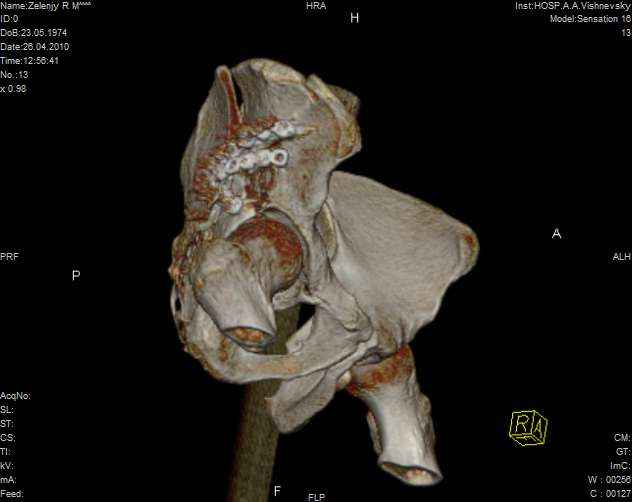

к таковым себя не причисляю, но...обычное дело для нашей страны - выкладывать 3D и не показывать стандартные проекции Judet. Дигност представляет те ракурсы, которые по-его мнению наиболее информативны, более того комп сам достраивает какие-то мелкие повреждения по 3D по своему усмотрению. По данной реконструкции можно предполагать высокий двухколонный перелом с оскольчатыми передней и задней колоннами, оскольчатую высокую переднюю колонну с задним полупоперечником или одно из перечисленных с вовлечение КПС. У меня впечатление за второй вариант, но нужно обследовать нормально - проекции, сканы.

высылаю дополнительно сканы.

Когда перелом не получается отнести к какому либо типу - эффективнее всего описать более детально. В дальнейшем проще бывает сортировать, и что важнее - "руководство к действию" бывает более обоснованным. В данном случае графа клинического диагноза может выглядеть так: Застарелый разрыв правого крестцово-подвздошного сочленения, консолидирующиеся со смещением переломы крыла и тела правой подвздошной кости, обеих колонн и задней гемисферы правой вертлужной впадины. Состояние после остеосинтеза.

Судя по представленным реконструкциям (не очень хорошего качества - много наводок)

мы имеем дело с полупоперечным переломом у которого отломался задний край или его отломали, превратив перелом в полный двухколонный.

По отдельным срезам и тем более по реконструкции трудно судить о сращении крыла и задней колонны с осевым скелетом.

Все выступающие коллеги высказались насчет необходимости стандартных снимков по Judet, потому что для определения тактики лечения переломов вертлужной впадины 3Д снимки малоинформативны.

Из того минимума, что представлено, мне кажется, мы имеем дело с двухколонным переломом вертлужной впадины. Обычно медиальный (центральный) "вывих" головки встречаются в сложных двухколонных переломах со смещением.